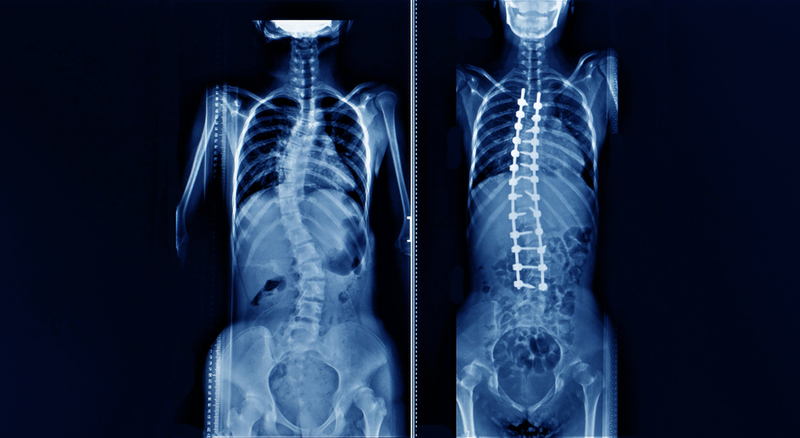

She borrowed the concept from other researchers who simulate how DNA molecules and proteins change their structure in response to a variety of factors. In the current study, Pasha drew on spinal X-rays of 129 adolescents with or without scoliosis. Computer analysis transformed those images into 2-dimensional (2-D) patterns, designated sagittal spinal profiles. She used those patterns to create S-shaped elastic rods in the computer simulation and applied simulated mechanical forces to observe how those rods deformed in 3-dimensional (3-D) shapes. The results were intriguing. Under this simulated mechanical force, S-shaped 2-D patterns in the model deformed into the 3-D patterns seen in scoliosis patients with the same sagittal curve.

However, the rods in the model that represented the sagittal curves of patients without scoliosis did not twist into a 3-D scoliosis-like deformation. This model provides strong evidence, said Pasha, that the shape of a person's sagittal profile can be a leading cause of scoliosis. Much research remains to be done, said Pasha, to determine whether the spinal shapes seen in images from younger patients can be developed into a risk-assessment tool to predict whether a 10-year-old is likely to develop scoliosis during their teenage years.

However, if follow-up studies verify that imaging studies can identify patients at risk for later scoliosis, these studies may allow clinicians to develop strategies to prevent a condition for which no preventive measures now exist. The current treatment for patients with severe scoliosis is to custom design a rigid spinal brace, with surgery as another option at a young age. It may be possible, said Pasha, that wearing a brace at a younger age may prevent scoliosis from developing.